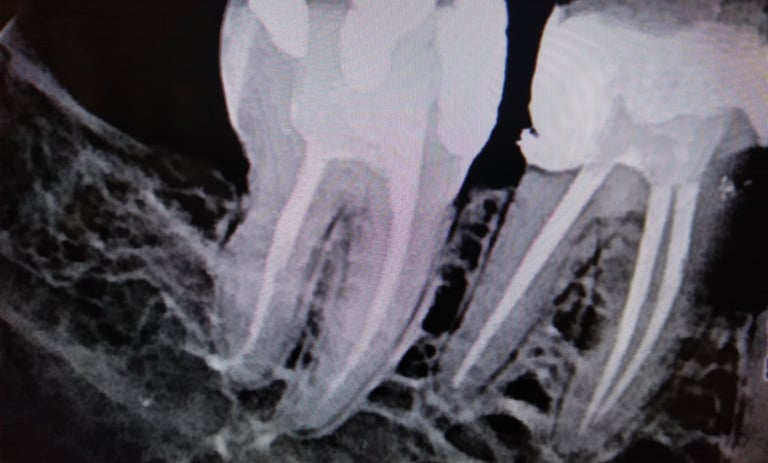

Endodontia é uma especialidade de odontologia. O endodontista é o responsável em realizar o tratamento de canal radicular. É o procedimento que faz a limpeza adequada nos condutos internos das raízes, removendo a polpa dentária inflamada e/ou infectada. Consiste na retirada total da polpa através da limpeza com soluções irrigantes e limas especiais, para depois preencher o interior das raízes com um material selador, que ajuda a manter a parte de dentro do dente livre de contaminação e assim promover a saúde bucal, evitando a perda prematura de um dente devolvendo a sua função estética e funcional.

Condutos Radiculares

Os condutos radiculares(canais) limpos garantem um maior índice de sucesso na endodontia.